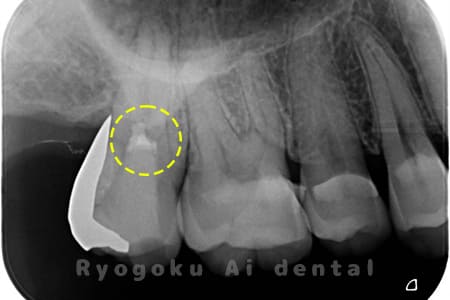

Case05

-

- 原因

- 15部重度カリエス

- 治療内容

- 断髄治療

- 治療費用

- 66,000円

歯がしみるとのことで来院された患者様です。虫歯が神経まで及んでいましたが、神経を一部分カットする断髄治療を行いました。経過も良好です。

<リスク・副作用>

術後は痛み、腫れ、痺れなどの副作用が生じる場合があります。症状が再発する可能性があります。その場合は抜髄する必要があります。